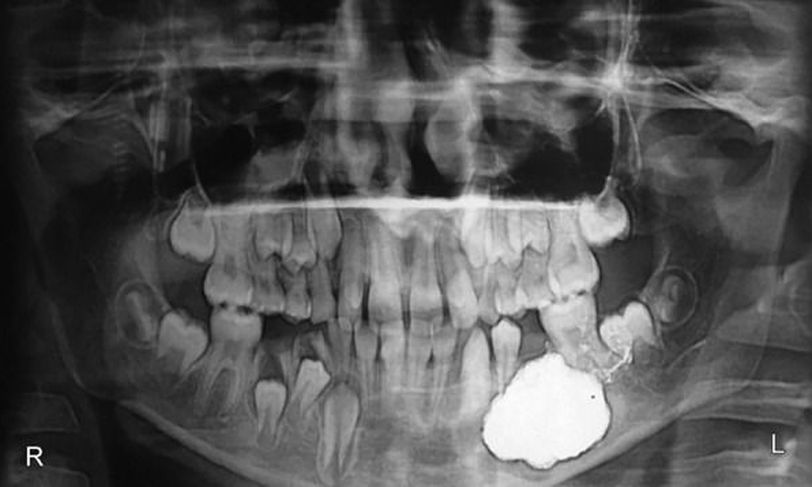

Dentigerous cysts are the most common type of odontogenic cysts associated commonly with unerupted or impacted teeth typically presented in the second or third decade of life. The case presented in this report is that a 10-year-old child with a hard submucosal swelling causing expansion of the buccal cortical plate. Radiographs revealed the presence of a well-defined radiolucency involving crowns of the impacted mandibular second left premolar and also the roots of adjacent teeth. The patient was treated with marsupialization of the cyst and extraction of the lower left second premolar along with preservation of involved teeth. This was followed by a space maintainer post operatively to prevent the space loss considering the age of this patient. Source: Bhardwaj B, Sharma S, Chitlangia P, Agarwal P, Bhamboo A, Rastogi K. Mandibular Dentigerous Cyst in a 10-Year-Old Child. Int J Clin Pediatr Dent 2016;9(3): 281-284.